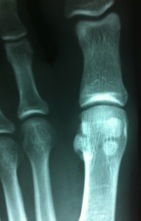

Notice the sesamoid on the left (lateral) is in 3 pieces and the sesamoid on the right (tibial) is in 2 pieces. (Dr. Nick’s Sesamoid Bones of right foot)